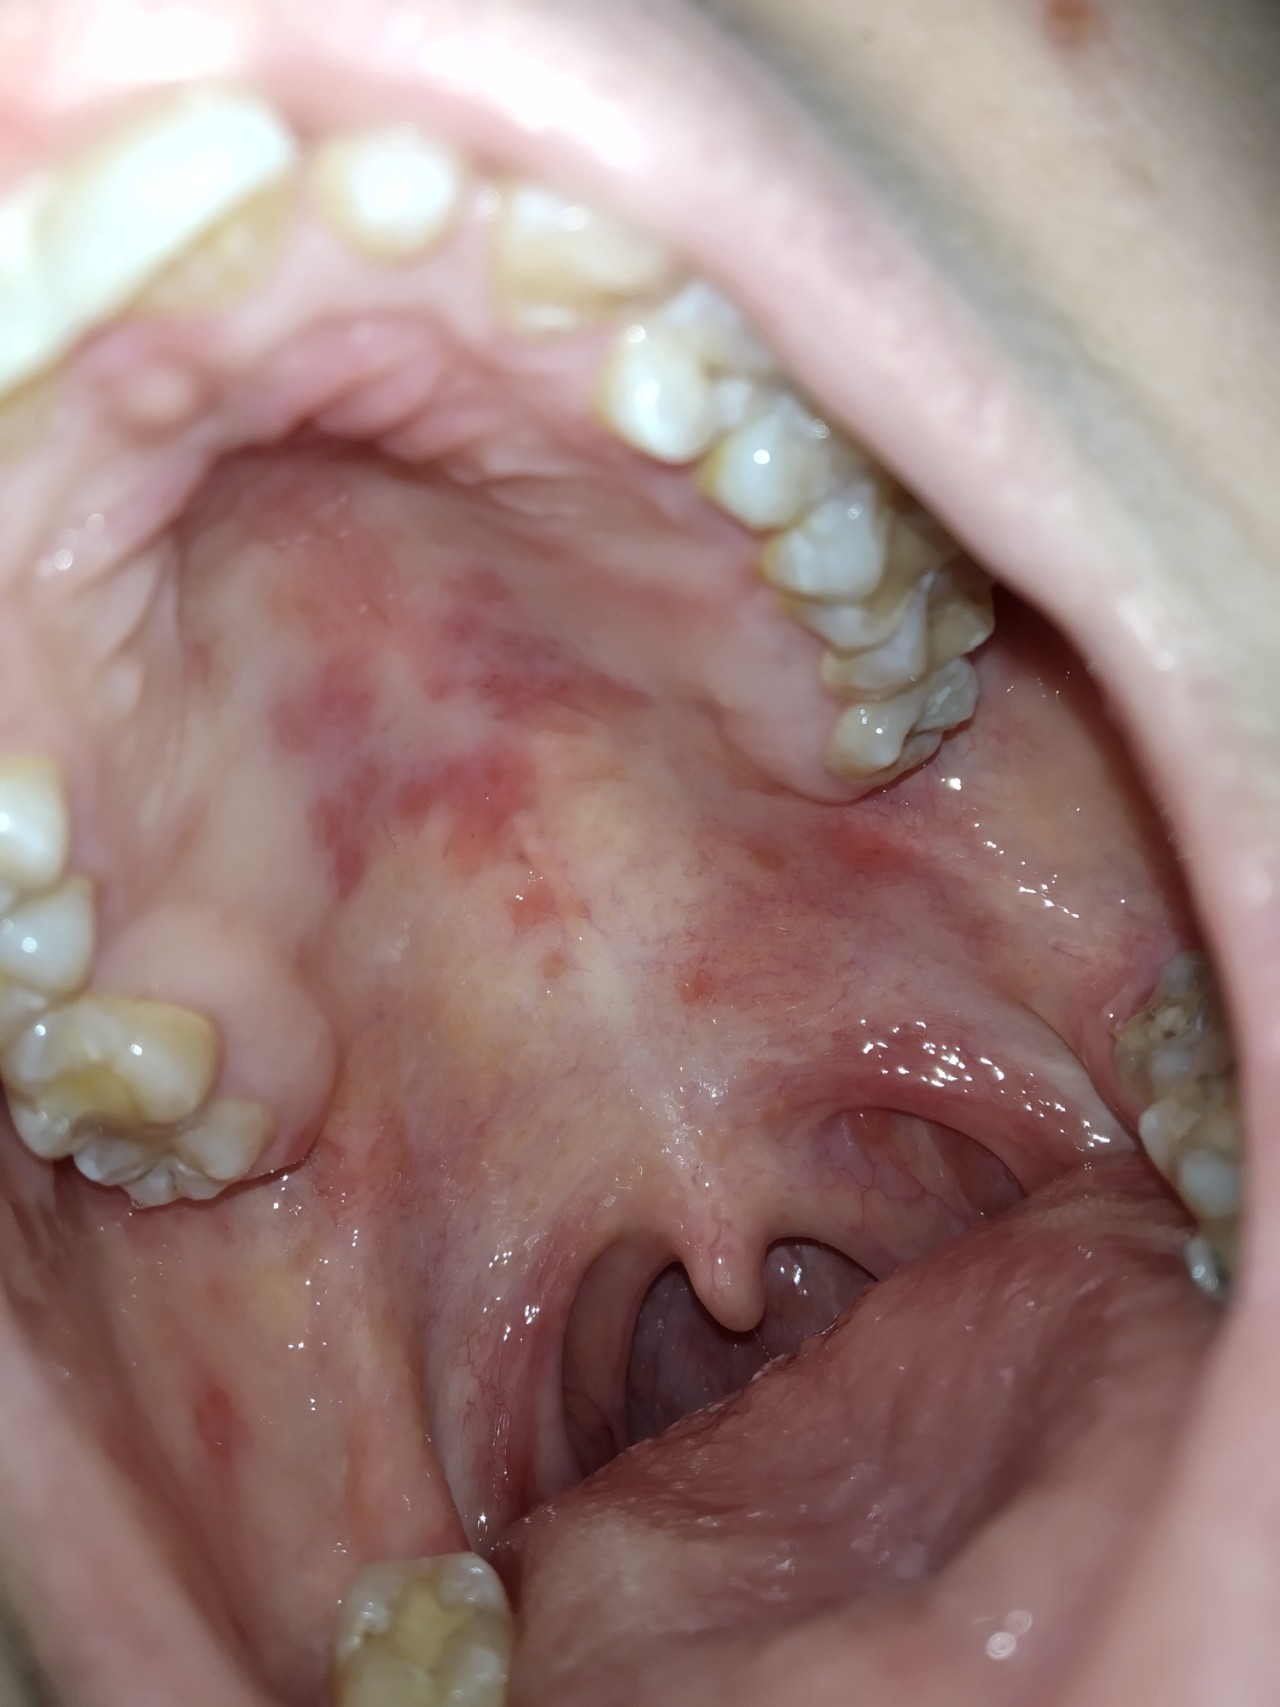

Здравствуйте, мне 28 лет, достаточно давно на небе появляются красные пятна, из количество то уменьшается, то увеличивается без видимых причин, скажите что это такое? Спасибо.

1. Заметила когда смотрела горло у меня хр тонзиллит и каждое утро я выдавливаю пробки из миндалин, пятна бывают появляются ниже, ближе к миндалинам на небе, так и заметила стала смотреть и увидела что на самом небе их много.2. ощущения никакие не вызывают 3Нет они никогда не исчезают полностью, одни проходят появляются другие, несколько элементов есть всегда, только когда то их немного а когда то все небо в пятнах

Здравствуйте.1Примерно 3-4 года может больше не знаю точно.2Да часто сдаю. Фото прилагаю.3. Принимаю постоянно необутин, синдром раздражённого кишечника, ношпу, и парацетамол в связи с женскими болями, у меня ьр астма редко Пульмикорт и редко Беродуал(по 2 недели раз в три месяца), сейчас принимаю нолицин антибиотик в связи с обострением цистита, так же почти ежедневно гастрофарм, Алмагель и гевискон суспензия, плюс от зр тонзиллита очень часто (почти каждый день) спрей Тантум верде, ингалипт, аджисепт таблетки.4. До и после удаления пробок все идентично, изменений нет, я не травмирую небо когда удаляю пробки.

У меня есть подозрение что у меня травмируется небо, от жёсткой пищи так как у меня дисплазия соеденительной ткани(и много сопутствующих заболеваний, к примеру пролапс митрального клапана, вегетативные расстройства, ранний остеохондроз и другие) В последние дни я кушала орешки со сгущенкой(домашняя выпечка) и появилось чувство что небо ободрано и усилились пятна. Может быть такое? Но такие ощущения есть не всегда, в основном пятна никак не беспокоят.

Предполагаю, что высыпания на небе - это проявления грибковой инфекции. Предлагаю сдать мазок с неба для посева на грибковых возбудителей с проведением теста чувствительности к противогрибковым препаратам.

"В последние дни я кушала орешки со сгущенкой(домашняя выпечка) и появилось чувство что небо ободрано и усилились пятна. Может быть такое? " - Может. Сгущенка - отличная пища для грибка.